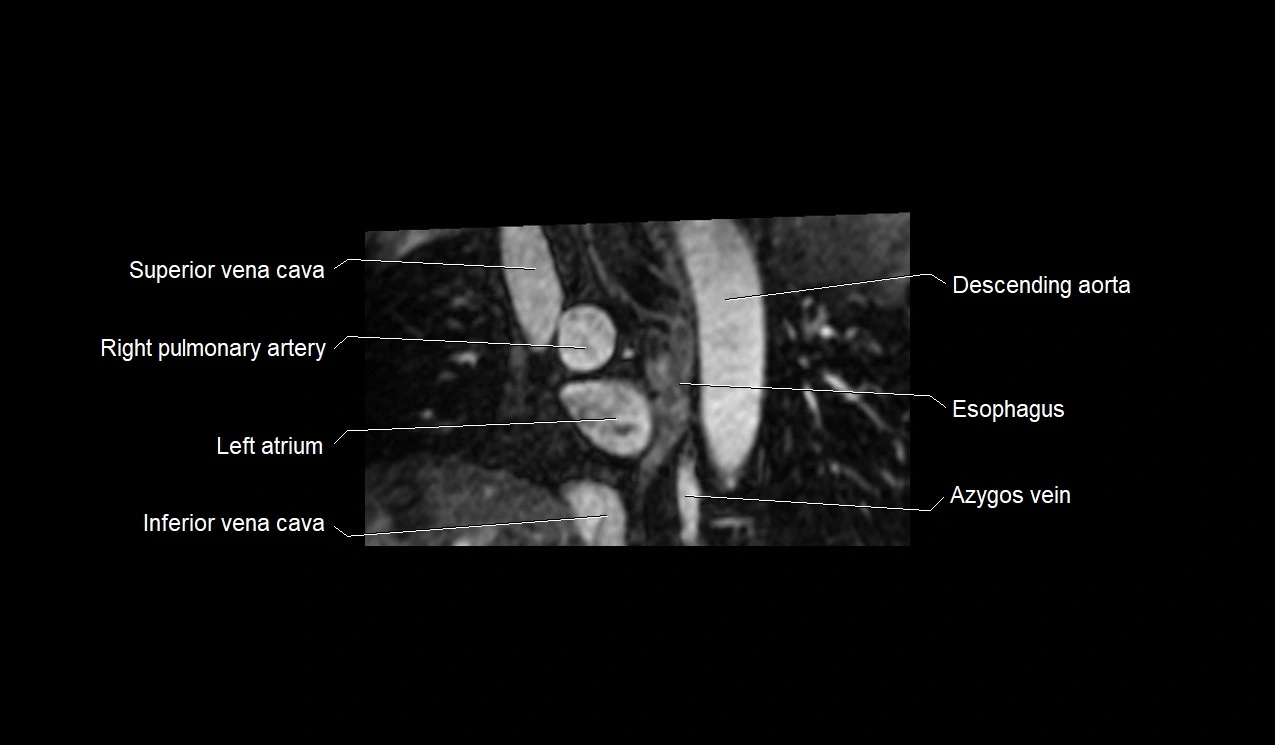

MRI image